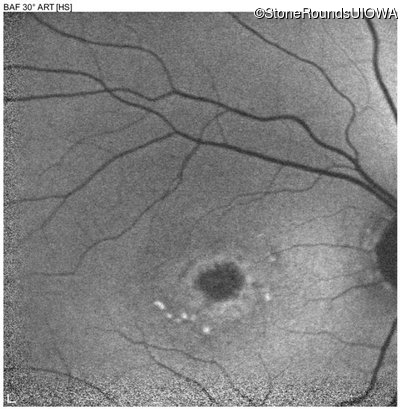

AR Stargardt Disease (IIA)

Age at visit: 54 years

This 54 year old woman first noticed reduced visual acuity in her mid 20's.

Diagnosis & molecular findings

Disease Gene Allele 1 variant(s) Allele 2 variant(s) Inheritance mode

AR Stargardt Disease ABCA4 Gly1961Glu GGA>GAA Cys2150Tyr TGT>TAT AR